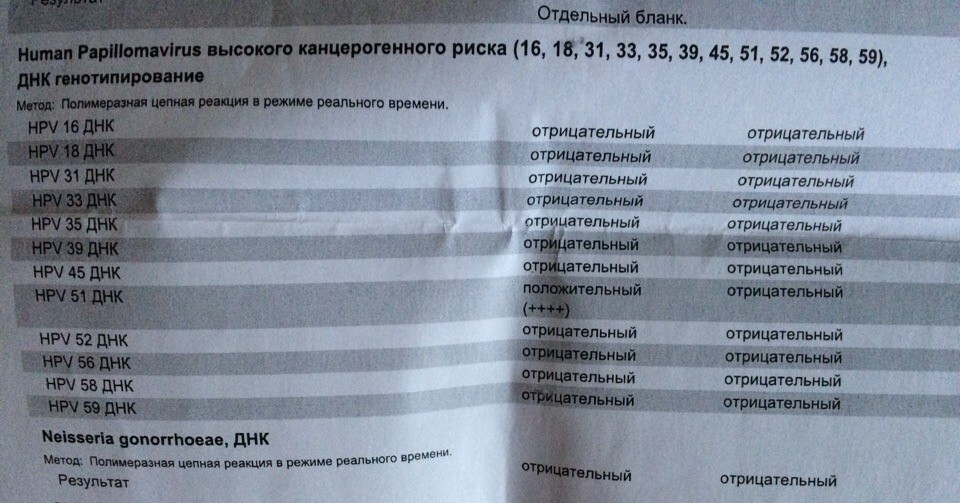

Факторы Риска ВПЧ: Визуальный Обзор и Информация